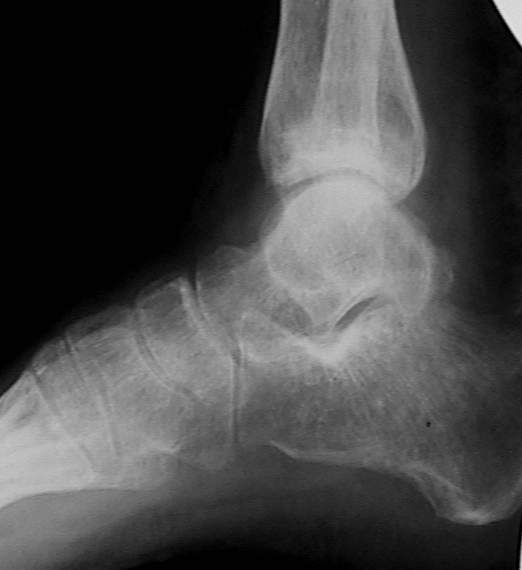

У больного травма в августе 2001 г. Лечился консервативно, Проводилась иммобилизация гипсовой лонгетой 3 мес. В последующем местное лечение. Остается контрактура боли в области наружной лодыжки. Направлен в наше отделение в конце января 2002 г Планируется костная аутопластика, остеосинтез пластиной, винтами перелома наружной лодыжки. Решается вопрос о коррекции неправильно сросшегося перелома внутренней лодыжки. Рентгенограммы: фас; профиль; план Сергей Зырянов

на снимке, кстати, срезан ее дистальный отдел, и правильность взаимоотношений с таранной костью не оценить. Если они правильные - я бы присоединился к мнению об оставлении ее покое.

А вот укорочение внутренней, похоже, привело к натяжению дельтовидной связки и гиперпрессии в медиальном отделе сустава, и уже сейчас там

видно сужение щели. Так что есть смысл обратить внимание на ортопедическую профилактику деформирующего артроза.

Не указан возраст, амплитуда движений, выраженность болевого синдрома.

А вообще - отдаленный исход хорошо сделанного артродеза голеностопного сустава по крайней мере не хуже исходов хорошо сделаных восстановительных операций. Так что если амплитуда движений сейчас меньше 40 градусов, и боли сильные - IMHO есть смысл расширить список

Надо сделать компьютерную томография и объектизировать истинное состояние переломов лодыжек. Пока не видно подвывиха таранной кости, а ложный сустав внутренней лодыжки (я его не вижу)в основном не вызывает функциональных растройств в голеностопном суставе.

Коллеги! Я думаю надо плясать от возраста, профессии, объёма движений и интенсивности болевого синдрома. Ничего подобного не прозвучало... Имеет место подвывих стопы кнутри, никем не отмеченный! Оно конечно варус лучше, чем вальгус, но в данном случае принципиально его устранение (если оперировать конечно). Если оперировать, то предлагаю: